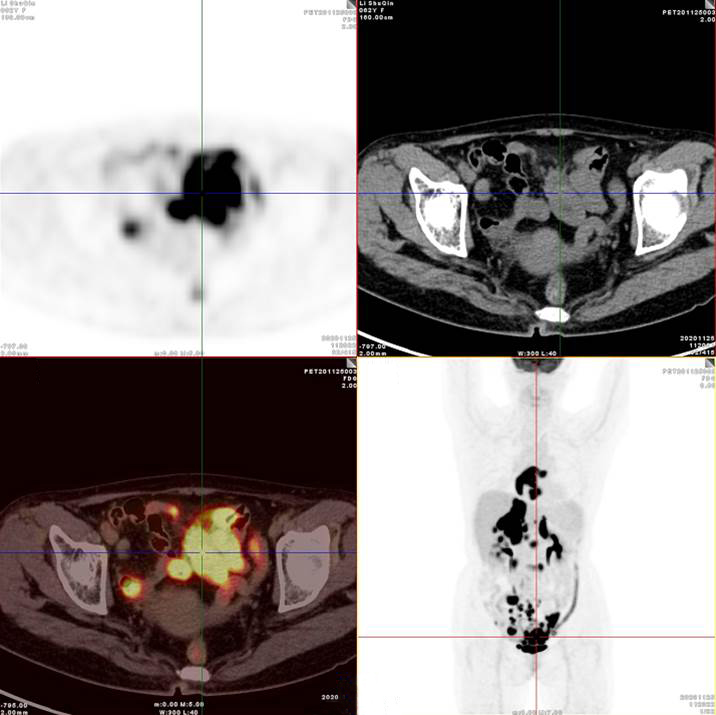

腸系膜多發(fā)淋巴結(jié)放射性攝取增高

多段小腸腸管放射性攝取增高